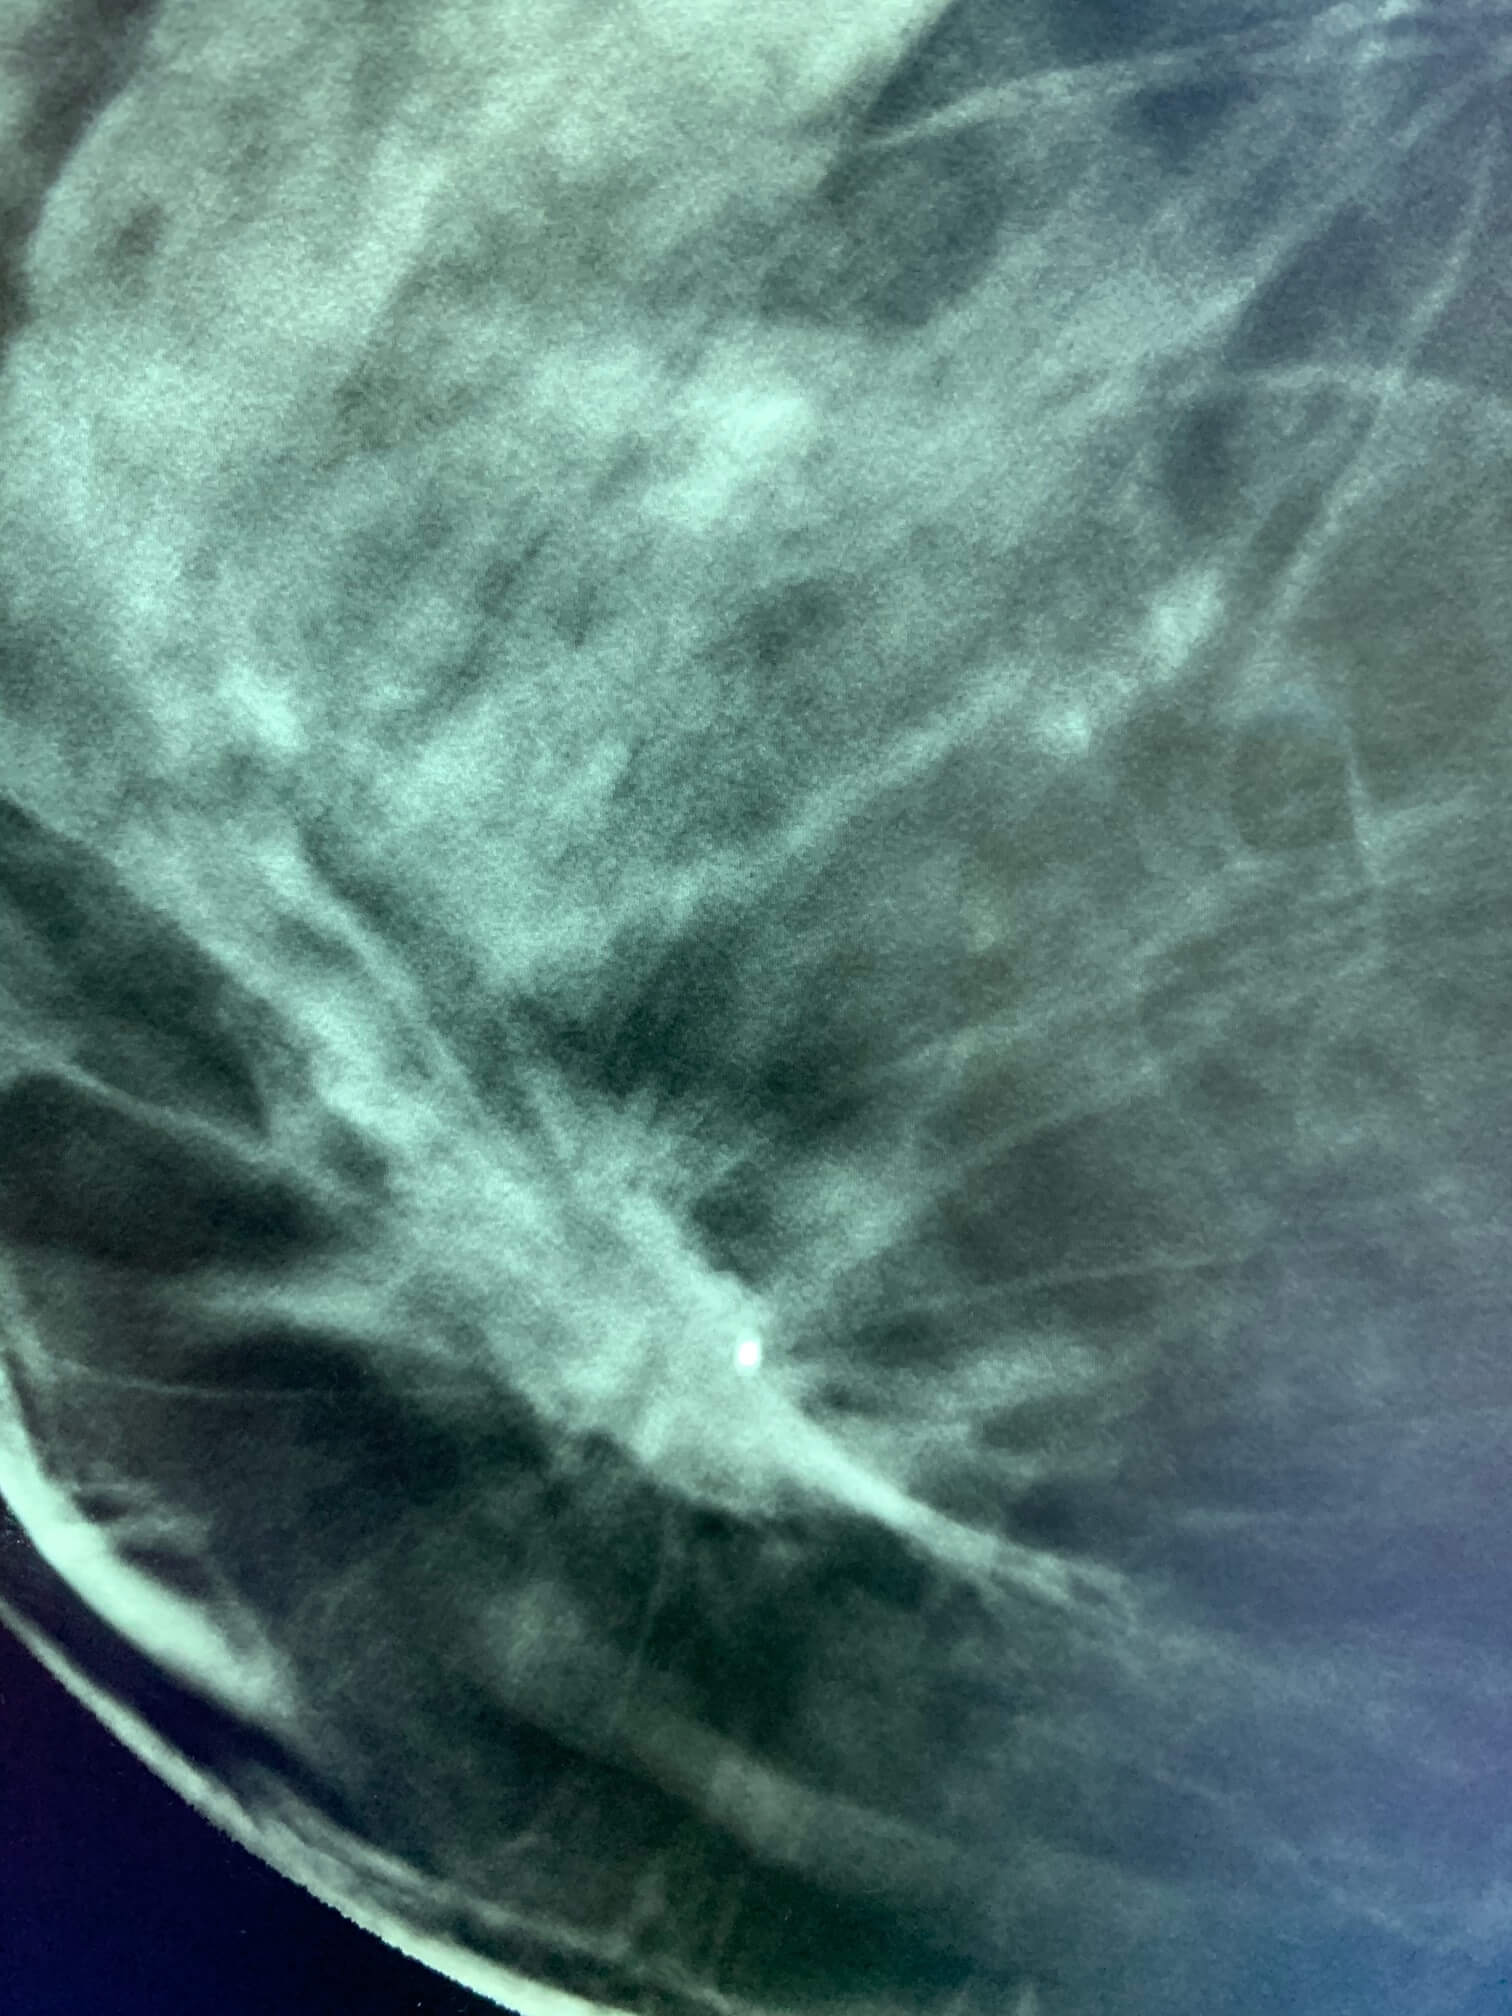

Woman, 56 years old. Screening mammogram.

MammoScreen™ points to a lesion of the inner inferior quadrant of the right breast.

The lesion pointed by MammoScreen corresponds to the lesion visualized in tomosynthesis with an architectural distortion.